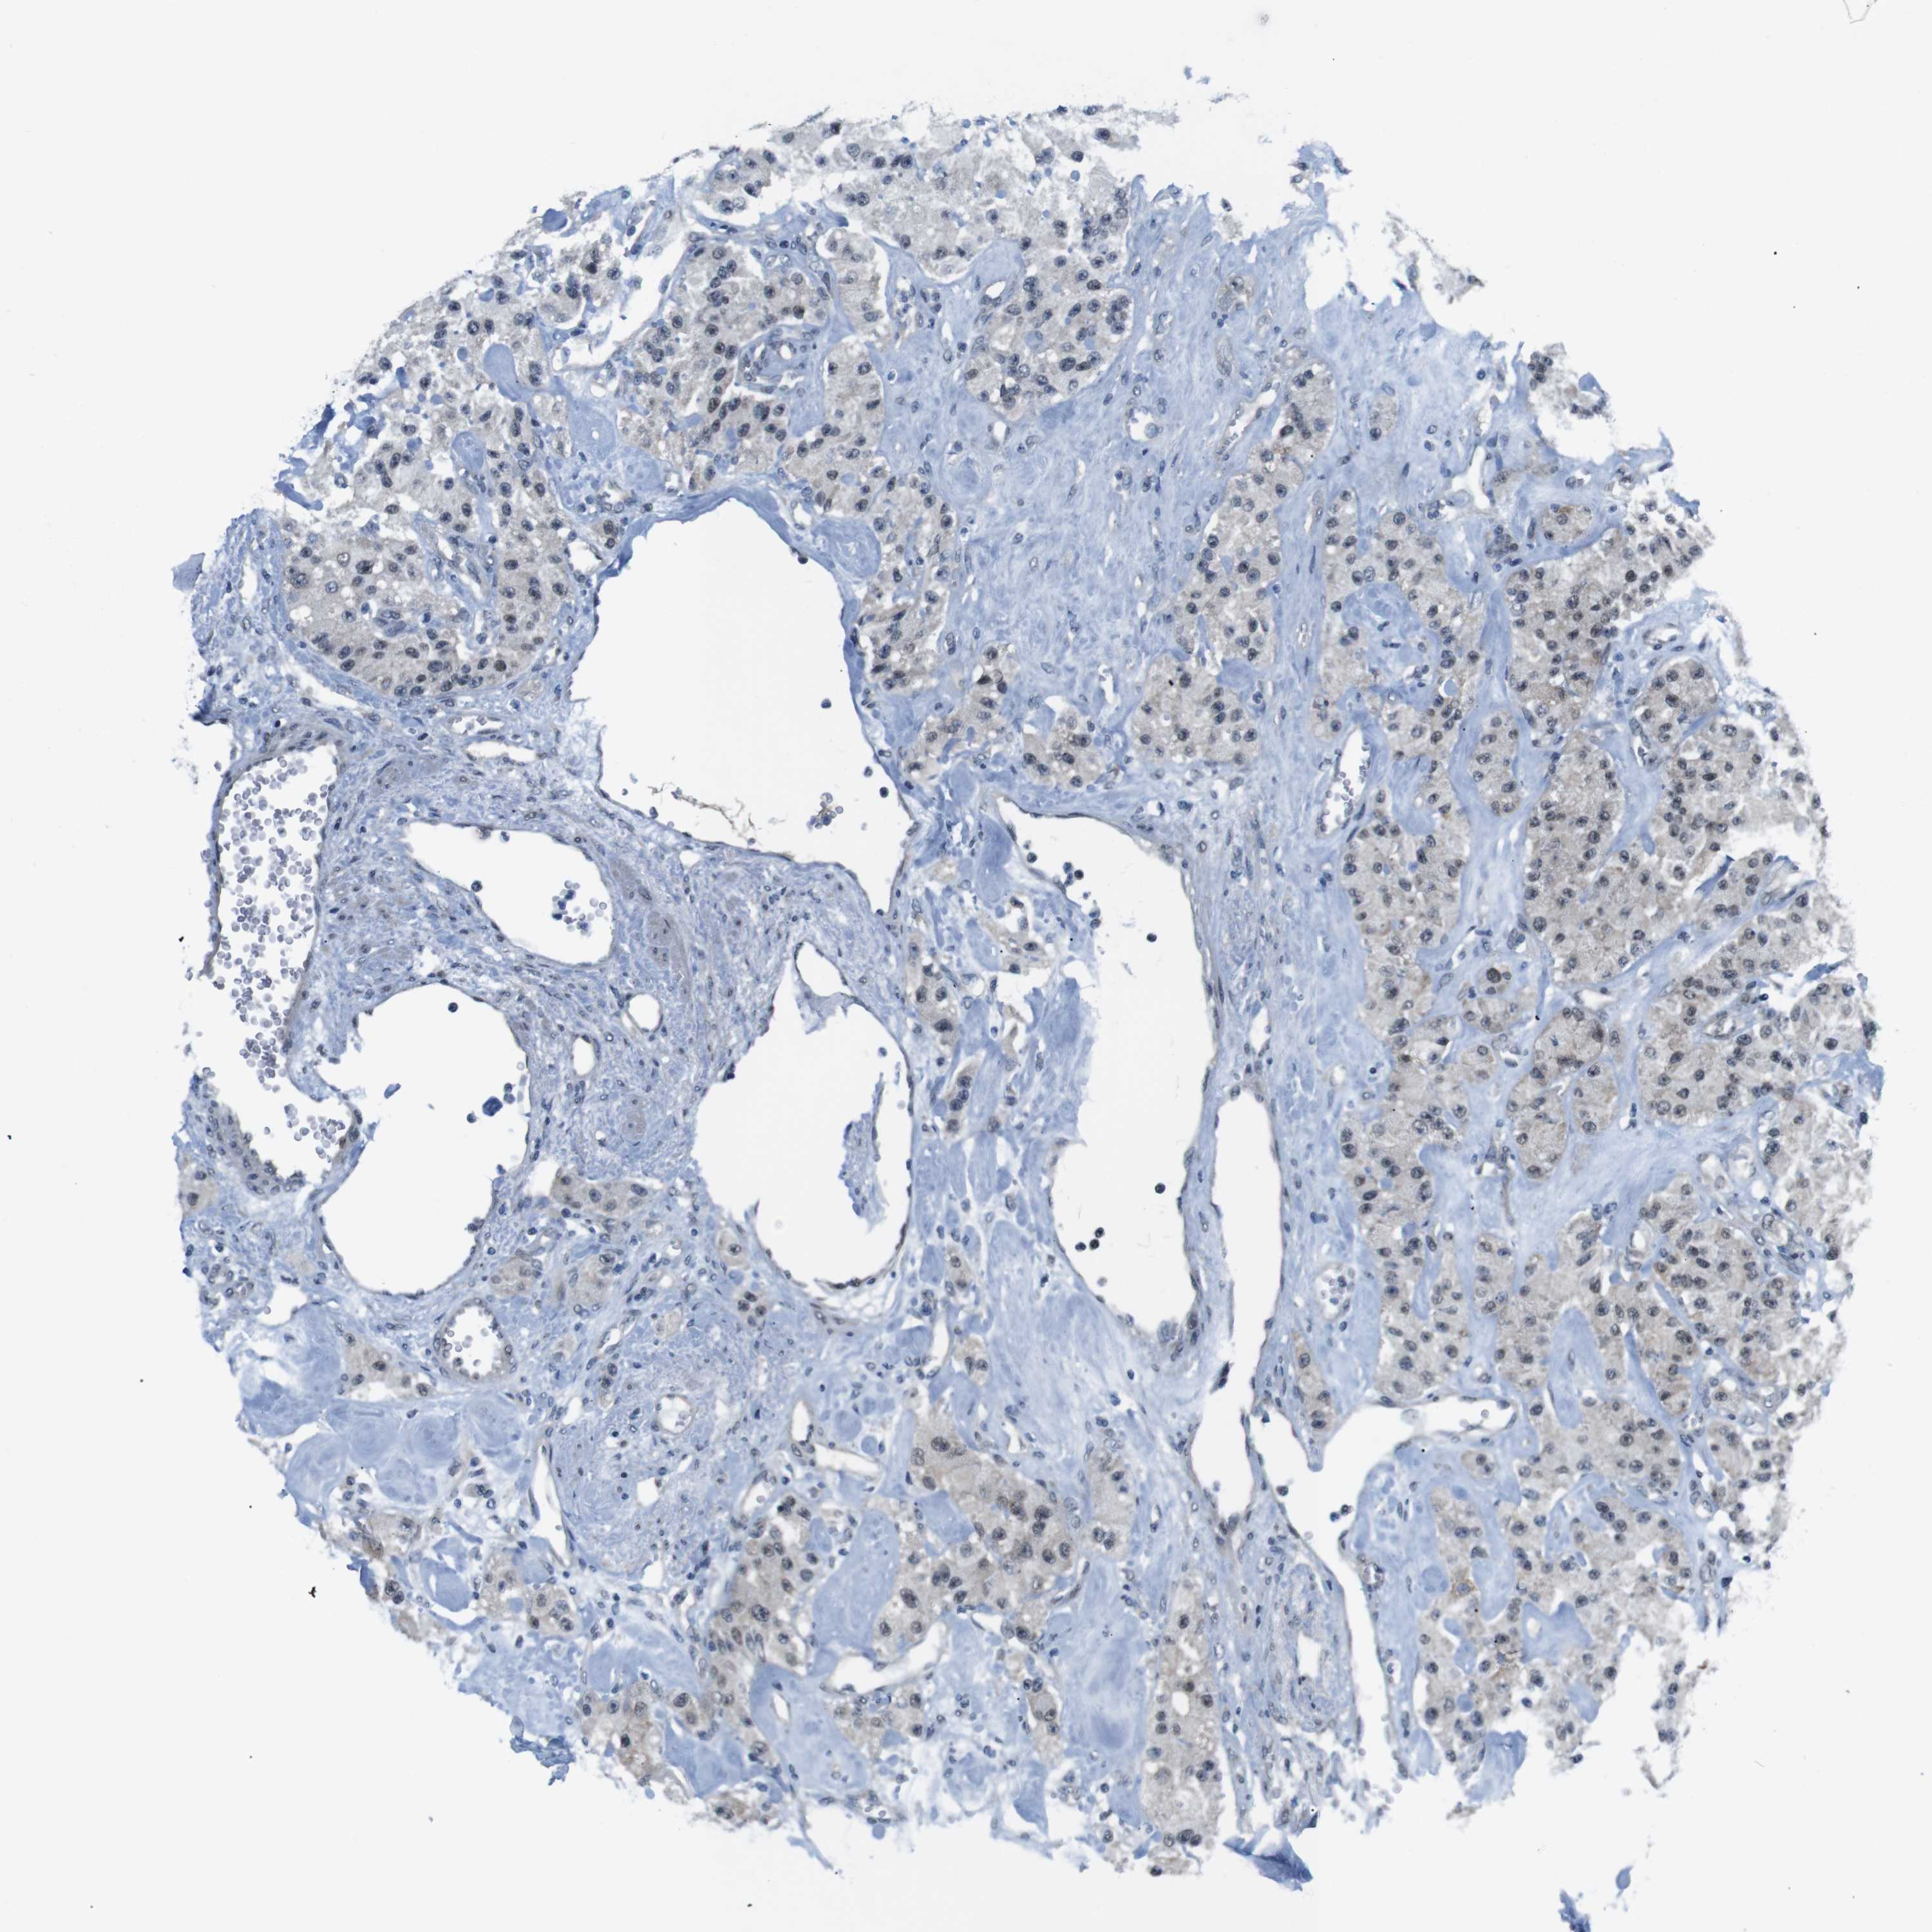

CARCINOID - Protein expressioni

A mouse-over function shows sample information and annotation data. Click on an image to view it in a full screen mode. Samples can be filtered based on level of antibody staining by selecting one or several of the following categories: high, medium, low and not detected. The assay and annotation is described here.

Antibody stainingi

Antibody staining in the annotated cell types in the current human tissue is reported as not detected, low, medium, or high, based on conventional immunohistochemistry profiling in selected tissues. This score is based on the combination of the staining intensity and fraction of stained cells.

Each image is clickable and will lead to virtual microscopy that enables deeper exploration of all samples and also displays staining intensity scores, fraction scores and subcellular localization as well as patient and tissue information for each sample.

Antibody HPA014366

Staining

High

Medium

Low

Not detected

Intensity

Strong

Moderate

Weak

Negative

Quantity

>75%

75%-25%

<25%

None

Location

Nuclear

Cytoplasmic/membranous

Cytoplasmic/membranous,nuclear

Carcinoid, malignant, NOS

Carcinoma, NOS